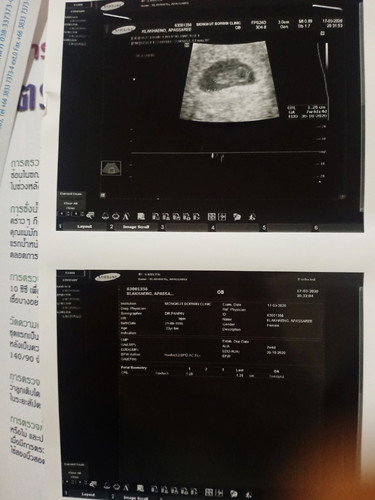

อาการเริ่มแรกมาจาก ตอนเช้าวันที่16 มีกาการปวดท้องจุกๆ ที่ก้นและอวัยวะเพศ สายๆมามีเลือดออก แค่ซึมๆสีดำ ช่วงเที่ยงเริ่มออกเยอะขึ้น จึงไปหาหมอ.คุณหมอซาวเจอตัวเด็ก. แต่ไม่มีคลื่นหัวใจ คุณหมอถามว่า เราตั้งครรภ์กีสัปดาห์ เราตอบว่า 9 สัปดาห์ คุณหมอจึงพูดว่าตัวน้องมีขนาดแค่1.28 เซนเองนะ ประมาณ7 สัปดาห์ ต่อด้วยคำพูดของคุณหมอที่ว่า ต้องรอดูอาทิตย์หน้านะครับว่าน้องยังอยู่รึเปล่า ถ้าน้องไม่มีการเจริญเติบโต และซาวหาหัวใจไม่เจอ คงต้องทำใจนะครับ. ต่อมาช่วงเย็ของวันที่ 17 เรามีเลือดสีแดงสด ออกมา เยอะกว่าในรูปนิดหน่อย. เราไปหาหมอที่คลีนิค. คุณหมอซาวให้บอกว่ายังเห็นตัวเด็กอยู่ แต่ก็ยังไม่ได้ยินเสียงหัวใจ เราควรจะรอน้องต่อไปไหมคะ. น้องจะยังอยู่รึเปล่า. ใครเคยเจอเคสแบบนี้บ้างคะ. คุยกันหน่อยจ้า